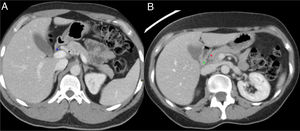

Hallazgos radiológicosComo la mayoría de las veces los pacientes presentan sintomatología de pancreatitis aguda, la prueba inicial suele ser una TC. Tanto la TC como la RM permiten una muy buena definición anatómica y delimitan muy bien la afectación inflamatoria en casos de PS (fig. 1). Además, dado que las lesiones pancreáticas son hipovasculares, si se realiza un estudio bifásico en el que se incluya una fase arterial con contraste, esta aporta más información que un estudio con una única fase portal, ya que de esta manera es posible identificar, además de los cambios inflamatorios, posibles lesiones en el parénquima pancreático que se visualizarán como áreas hipocaptantes. El diagnóstico diferencial de estas incluirá lesiones neoplásicas o áreas de necrosis en un contexto de pancreatitis.

Anatomía normal del surco pancreaticoduodenal (PD). Cortes axiales del abdomen tras administración de contraste intravenoso en fase portal (A y B). Surco PD: espacio comprendido entre el colédoco (asterisco azul, A), la arteria hepática común (asterisco negro, A), la cabeza del páncreas (asterisco rojo, B) y la segunda porción duodenal (asterisco verde, B).

Paciente de 54 años ingresada por episodio de pancreatitis aguda. Cortes axiales del abdomen con contraste intravenoso en fase portal. A) Aumento de tamaño de la cabeza pancreática con borramiento del surco pancreaticoduodenal (asterisco rojo). B) Ectasia del conducto pancreático principal y colédoco distal (flecha verde) con defecto de repleción en la vena porta en relación con trombosis portal (flecha negra). Hallazgos en probable relación con pancreatitis del surco.